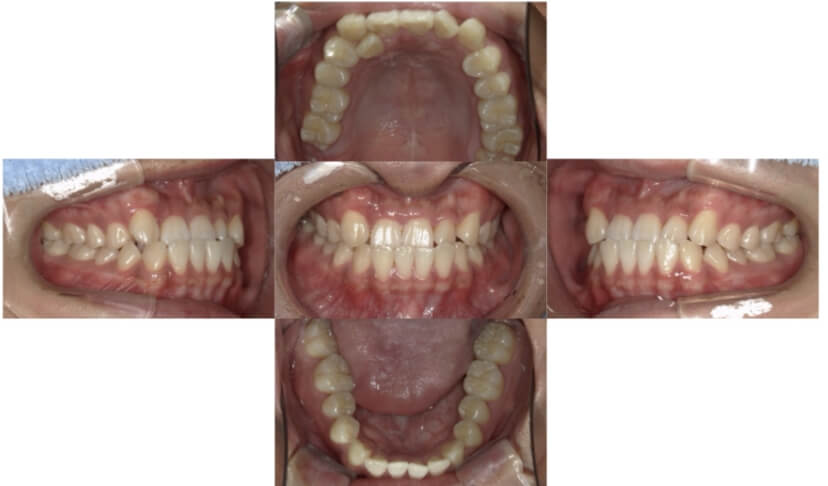

症例2

上下顎前突、叢生

抜歯

ブラケット矯正

上下顎前突、叢生(上下出っ歯、上下の前歯のガタガタ)のケースです。

装置はラビアル(上下表側)で、上下顎の小臼歯を4本抜歯を行っています。抜歯したスペースを使って、上下の前歯の後方移動と叢生(ガタガタ)の改善を行っています。

主訴 前歯のガタガタと口元がでているのが気になる。

年齢・性別 30歳 女性

お住まいの地域 東京都大田区

治療方針 抜歯スペースを利用して上前歯の叢生(ガタガタ)と口元突出の改善

抜歯部位 上下顎左右第一小臼歯

使用装置 ラビアル(上下表側)、顎間ゴム

治療期間 1年11か月

治療回数 13回

リテーナー クリアリテーナー

BEFORE

AFTER